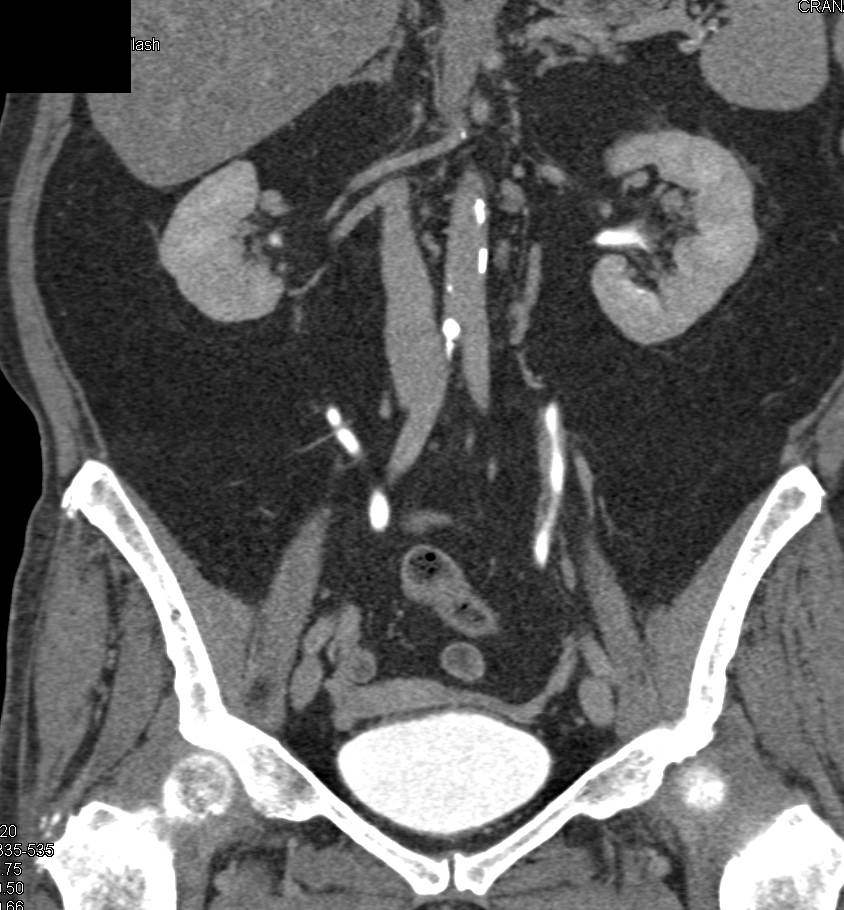

Transitional Cell Carcinoma of the Left Ureter